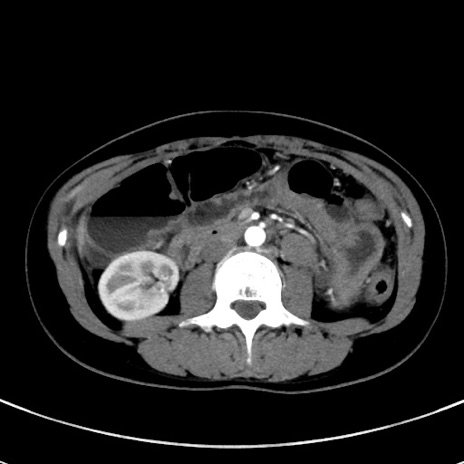

症例17(横断像)

【症例】20歳代女性

【主訴】嘔吐、下腹部痛

【現病歴】昨日夕食後に嘔吐し下腹部痛が出現。本日になっても嘔吐持続し改善しないため来院。

【身体所見】意識清明、BT 37.2℃、BP 108/67mmHg、腹部:平坦、やや硬、下腹部正中から右にかけて圧痛あり、反跳痛軽度あり、tapping pain(+)。

【データ】WBC 13600、CRP 14.94